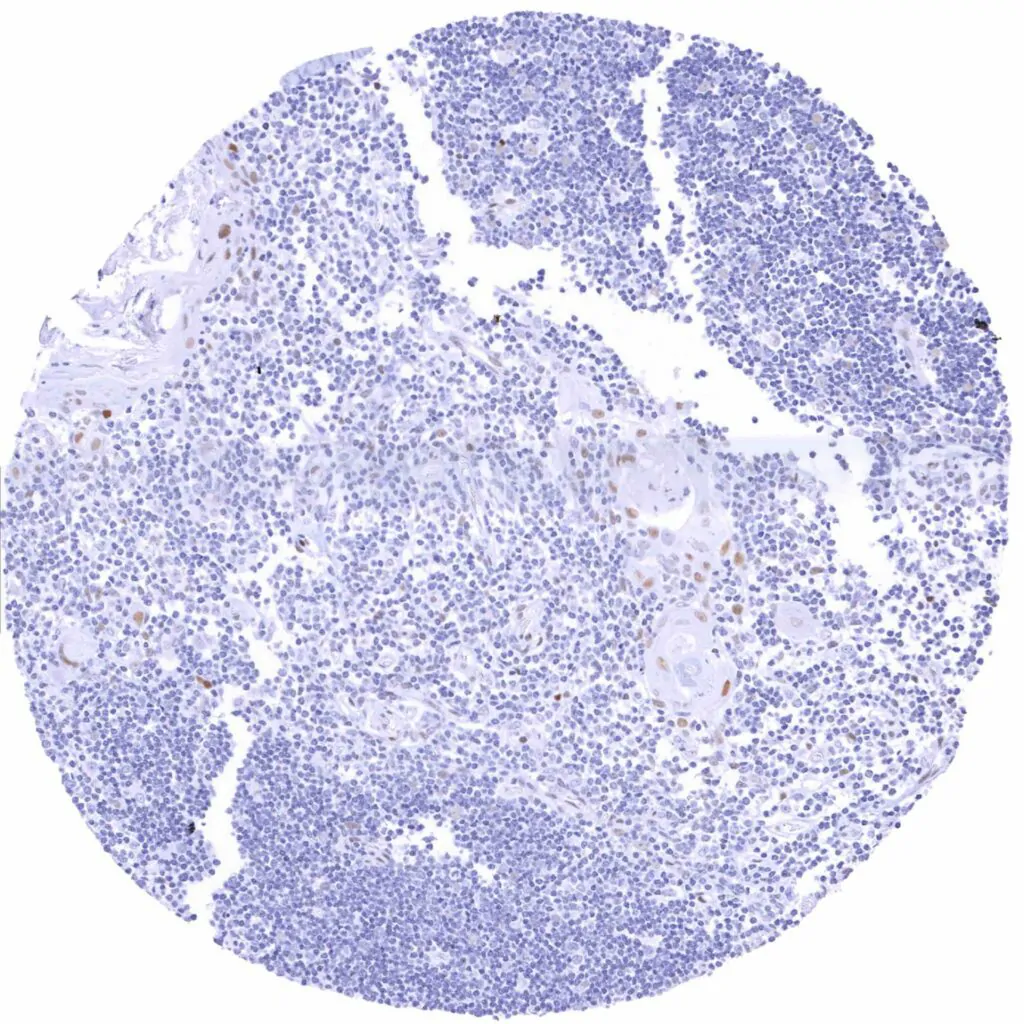

Tonsil – Weak to moderate TLE1 staining in a subset of lymphocytes, predominantly in germinal centres. Moderate TLE1 staining of a major subset of crypt epithelial cells